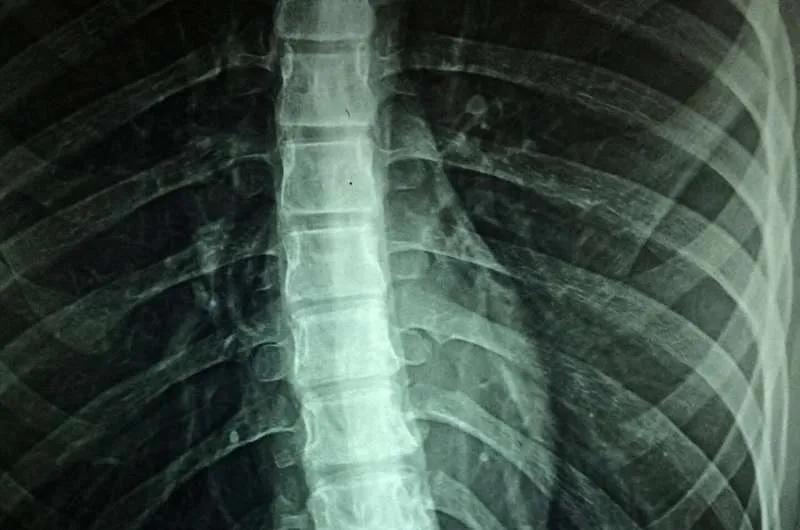

Texas: The spinal cord is more difficult to access and research than the brain. The difficulties posed by its mobility and anatomical structure have made it difficult to determine exactly how it acts.

In the brain, the distribution of neurons, or gray matter, and the bundles of nerve fibers known as white matter is the exact inverse of spinal cord anatomy.

“We typically refer to this as the ‘inside-out anatomy’ of the spinal cord,” said Lan Luan, an assistant professor of electrical and computer engineering and co-investigator on the grant. “The outer layer of the brain ? the gray matter ? is where the neurons are, whereas the fibers called white matter are on the interior. In the spinal cord, the white matter or fibers are on the exterior, shielding the neurons. This makes accessing those neurons more challenging.”

To ensure better access, scientists plan to develop a probe design that is small enough to be implanted at different sites on the spine yet has greater depth coverage and enough channels to capture data from neurons in a spinal cord cross section.